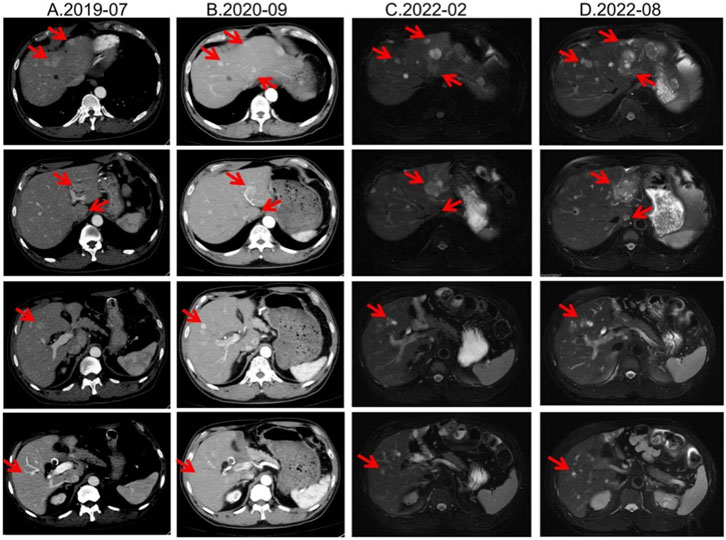

Second-line therapy began in September 2022, with surufatinib 300 mg daily. In the SANET III phase III trial, surufatinib significantly prolonged PFS in pNETs (Xu et al., 2020). The MRI efficacy evaluations in January, June, and September 2023 all demonstrated SD (Figure 2). During treatment he developed mild-to-moderate proteinuria and anemia (hemoglobin 78 g/L). Considering the patient experienced intermittent melena in September 2023, after MDT discussion and temporary drug discontinuations he was screened for the “[177Lu]Lu-DOTATATE Injection versus Long-Acting Octreotide Study”. [68Ga]Ga-DOTATATE imaging demonstrated that some hepatic metastases were SSTR-negative, and he therefore failed screening (Figure 3). Surufatinib was resumed at a reduced dose of 200 mg daily. On 8 January 2024, the patient passed approximately 200 mL of dark red stool. A gastroscopy revealed multiple small-intestinal ulcers at the gastroenteric anastomosis site (A1 stage, Forrest III). After a comprehensive evaluation of efficacy and safety, surufatinib was discontinued.

MRI scans in three columns, labeled A.2023-01, B.2023-06, and C.2023-09, showing liver changes over time. Each column contains four images with red arrows indicating specific areas of interest, likely abnormalities or changes in the liver tissue.

Figure 2. Lesion changes in patients treated with second-line surufatinib. (A) 2023-01 MRI: Multiple enhanced nodular shadows in the liver, with the larger ones located in the left lateral lobe of the liver, approximately 4.4 cm × 3.5 cm in size. Treatment response evaluation: SD. (B) 2023-06 MRI: Multiple enhanced nodules in the liver, with the larger ones located in the left lateral lobe of the liver. Treatment response evaluation: SD. (C) 2023-09 MRI: Multiple enhanced nodules in the liver, with the larger ones located in the left lateral lobe of the liver. Treatment response evaluation: SD.